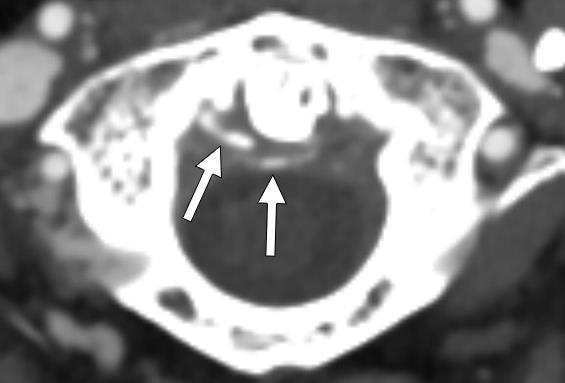

381 A Diagnosis Fit for a Queen: Crowned Dens Syndrome

10.SnyderAandSchmalzleSA.Spontaneous Streptococcuspyogenes pelvicinflammatorydisease;casereportandreviewoftheliterature. IDCases. 2020;20:e00785.